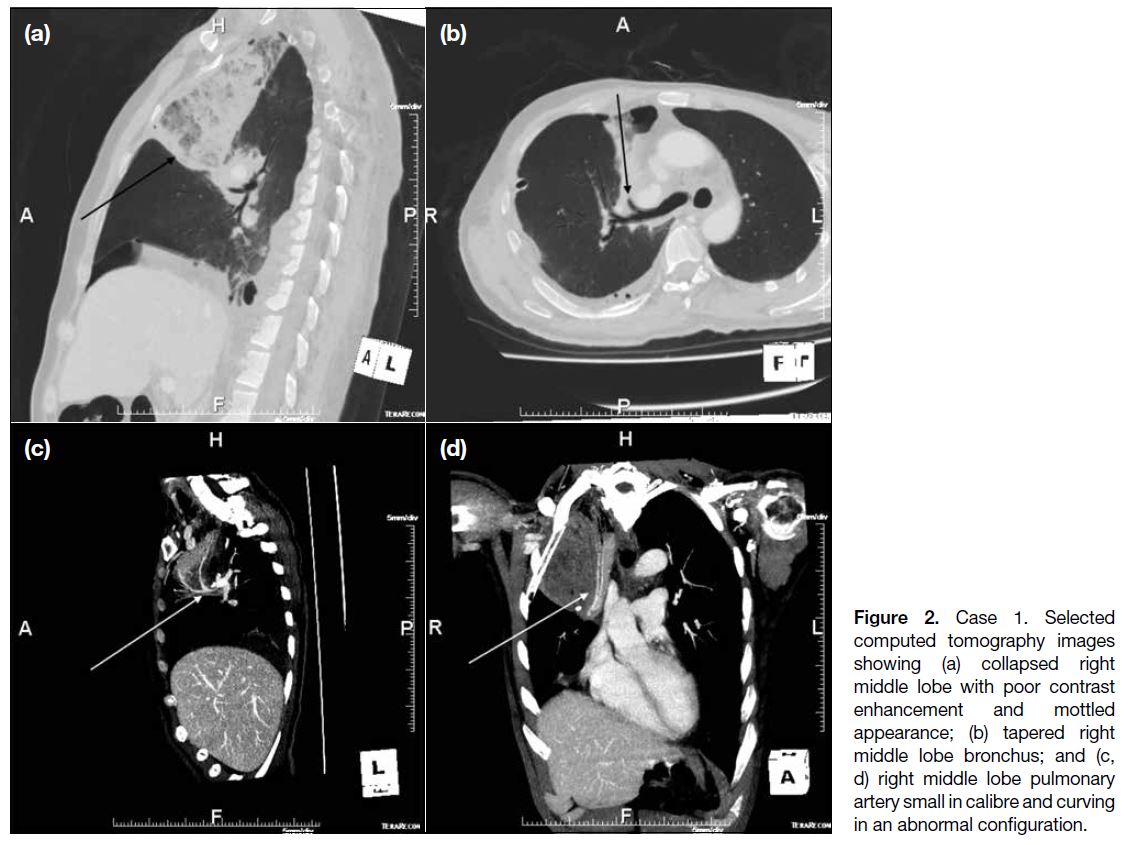

showed collapse consolidation of the right middle lobe

with poor contrast enhancement and mottled appearance

(Figure 2a). The right middle lobe bronchus appeared tapered with abrupt termination (Figure 2b). The right

middle lobe pulmonary artery also appeared small in

calibre and curved in an abnormal configuration (Figure 2c and d). With the suspicion of lung torsion, explorative

Figure 2. Case 1. Selected

computed tomography images showing (a) collapsed right middle lobe with poor contrast enhancement and mottled appearance; (b) tapered right middle lobe bronchus; and (c, d) right middle lobe pulmonary artery small in calibre and curving in an abnormal configuration.